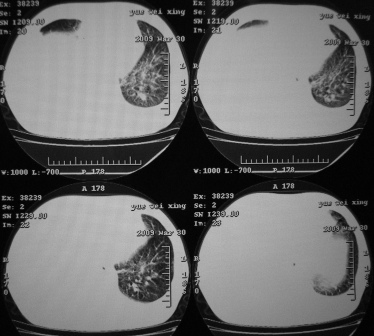

xx 男 43岁

右下叶支气管变窄闭塞,右下叶实变,双肺野弥漫性斑片状影,肺纹理增多增粗,纵隔多发淋巴结肿大,双侧胸水,考虑1双肺继发型结核,右下叶支气管内膜结核,双侧胸水2右下叶中央型肺癌伴右下叶实变,双肺转移,纵隔淋巴转移,双侧胸腔积液3淋巴瘤,请结合病史进一步检查。

1)考虑右侧中央型肺癌伴右肺下叶不张,双肺及纵隔淋巴转移。2)双侧胸腔积液,以右侧为甚。3)心包积液。